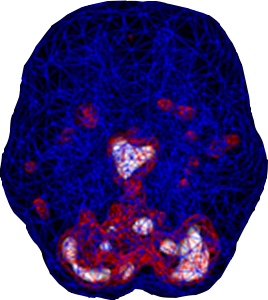

SPECT (single photon emission computed tomography) is a nuclear medicine study that evaluates blood flow and activity in the brain. Basically, it shows three things: healthy activity, too little activity, or too much activity. A healthy “active” scan shows the most active parts of the brain with blue representing the average activity and red (or sometimes red and white) representing the most active parts of the brain. In the healthy scan on the top right, the most active area is in the cerebellum, at the back/bottom part of the brain. The brain scan below it shows overactivity in the deep limbic system (the brain’s emotional center), a pattern commonly seen in depression.

Depressed Brain Scan